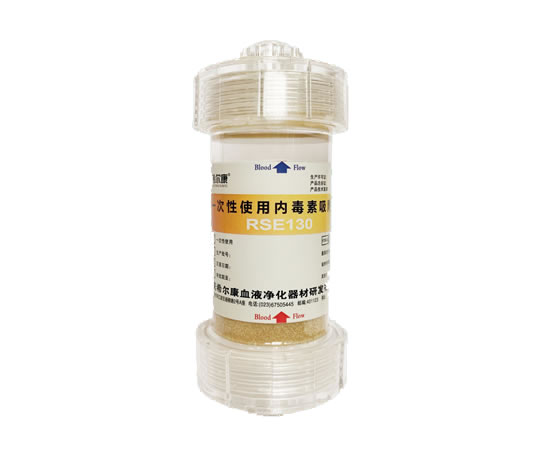

一次性使用内毒素吸附柱

在研产品

一次性使用内毒素吸附柱

主要用于 “内毒素血症”,救治多器官功能衰竭所致的各种危急症。